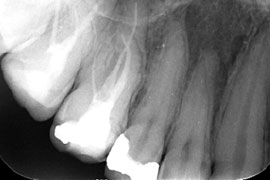

wurzelgefüllter Zahn mit Entzündung an der Wurzelspitze; zusätzlich ist eine abgebrochene Feile zu sehen

Um den betroffenen Zahn dennoch zu erhalten besteht die Möglichkeit eine erneute Wurzelkanalbehandlung, eine sogenannte Revisionsbehandlung, durchzuführen. Dies kann notwendig sein, wenn:

Der Zahn wird mittels eines Spanngummis isoliert, die Hohlräume werden aufgesucht und das vorhandene infizierte Füllmaterial wird entfernt. Dann erfolgt die erneute Reinigung, die bei einer Revisionsbehandlung oftmals schwieriger und zeitaufwändiger ist. Unter Berücksichtigung des Einzelfalles wird in das gereinigte Wurzelkanalsystem bis zum folgenden Termin vielleicht ein Medikament eingebracht. Zur Behandlung kann es nötig sein eine vorhandene Krone oder Brücke zu entfernen, um das Wurzelkanalsystem zu erreichen.

1. Entfernung von 2 Fragmenten aus mb1

2. Revision und Perforationsdeckung bei via falsa